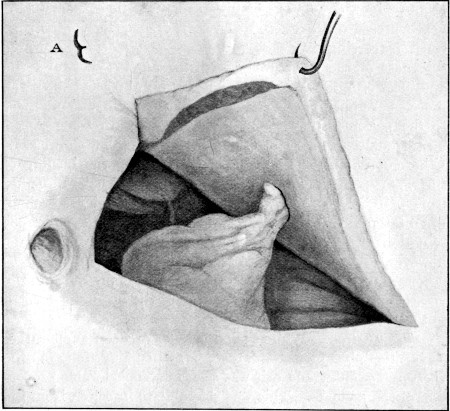

25b. Prolapsed Omentum77

89. Impaction of Omentum in Exit Wound of Abdominal Wall421